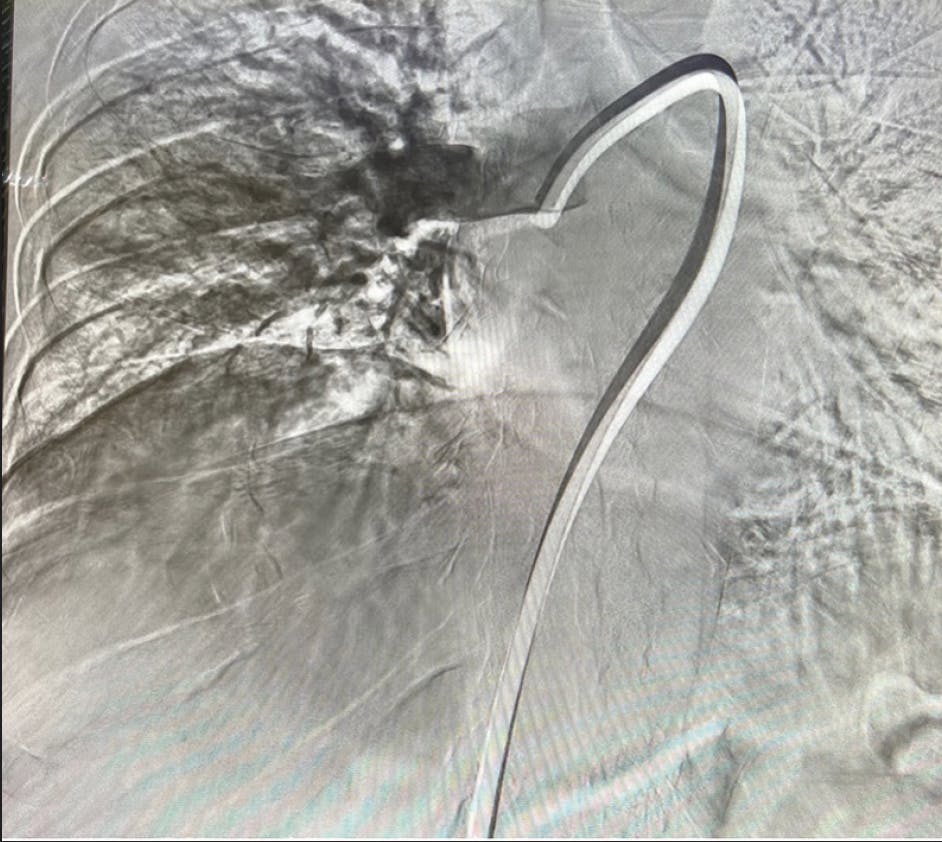

Based on evaluation, we decided to pursue aspiration thrombectomy utilizing Lightning Flash through a 16-F, 65-cm Gore DrySeal sheath (Gore & Associates). We achieved access in the right femoral vein. The device time was 17 minutes, and the total procedure time was 30 minutes (Figure 3, Figure 4, Figure 5, and Figure 6). At the conclusion of the case, the total EBL was 175 mL, the patient had BP of 112/67 mm Hg, HR of 65 bpm, and oxygen saturation of 99% on 3 L nasal cannula.

Figure 3. Post-thrombectomy lower right lobe angiogram.

Figure 4. Post-thrombectomy upper right lobe angiogram.

INTERVENTION

After initial evaluation, the decision was made to use aspiration thrombectomy to remove the PE thrombus. We utilized a 16-F, 65-cm Gore DrySeal sheath through the right femoral vein. Penumbra’s Lightning Flash was used for a device time of 10 minutes (Figure 3, Figure 4, and Figure 5). The total procedure time was only 20 minutes. With the conclusion of the case, we had an EBL of 120 mL and a postprocedure BP of 120/87 mm Hg. The HR decreased substantially to 98 bpm, and the oxygen saturation improved to 100% on room air.

Figure 3. Right post-thrombectomy angiogram.

Figure 4. Left post-thrombectomy angiogram.